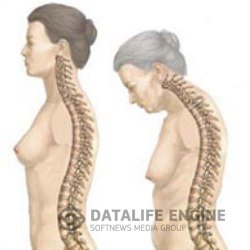

Особо следует выделить результаты исследований ученого А.А.Богомольца, который обратил внимание на роль соединительной ткани в процессе старения. И на самом деле, ткань эта заслуживает самого пристального внимания. Прежде всего, следует отметить, что в организме она являете поистине вездесущей, поскольку представляет собой, по сути дела, остов тела.

На первый взгляд, соединительная ткань -это наименее важные элементы нашего организма: всевозможные волоконца, пленки, соединяющие или разъединяющие мышцы, железы и другие органы. Однако эта малоприметная ткань проникает в самые отдаленные закоулки организма, сама по себе или с кровеносными сосудами. Она присутствует в костях, мышцах, в суставах, железах, в жировой ткани и мозге.

Характерным для соединительной ткани является и то, что она не дифференцирована, что у нее нет постоянного и единообразного клеточного состава, как, например, в мышечной, жировой или костной ткани. Клетки соединительной ткани очень "самостоятельны". Прежде всего они большие непоседы. Особенно это относится к клеткам-макрофагам. Как только где-либо в организме появляется чужеродное тело, макрофаги немедленно отправляются к месту вторжения с целью "ликвидации опасности". Если это бактерии, то макрофаги их просто "проглатывают" и тем самым уничтожают. Если это, например, угольная пыль, осевшая в легких, макрофаги поглощают ее, стараясь изолировать вторгшееся вещество от тканей организма. Если это крупное инородное тело, например, осколок снаряда, то макрофаги образуют вокруг него своего рода плотный оборонительный вал, полностью изолируя его от окружающих тканей. Кроме того, клетки соединительной ткани ремонтируют любые возникшие поломки: они участвуют в процессе срастания костных переломов, образования рубцов в местах, где были раны, и так далее.

Неудивительно поэтому, что А.А.Богомолец обратил внимание на эту чрезвычайно важную ткань. Притом ученый задался вопросом: а что происходит, когда разбросанная по всему организму соединительная ткань сама начинает болеть и стареть? Ведь совершенно очевидно, что любой дом, даже сложенный из самых лучших и прочных кирпичей, рухнет, когда станет портиться и распадаться соединяющий эти кирпичи раствор. И вот А.А.Богомолец выдвинул смелую гипотезу, утверждающую, что "возраст организма - это возраст его соединительной ткани", другими словами, организм до тех пор будет здоровым, жизнеспособным и молодым, пока его соединительная ткань, и прежде всего самый ценный элемент этой ткани - макрофаг, будет охранять молодость и жизнеспособность.